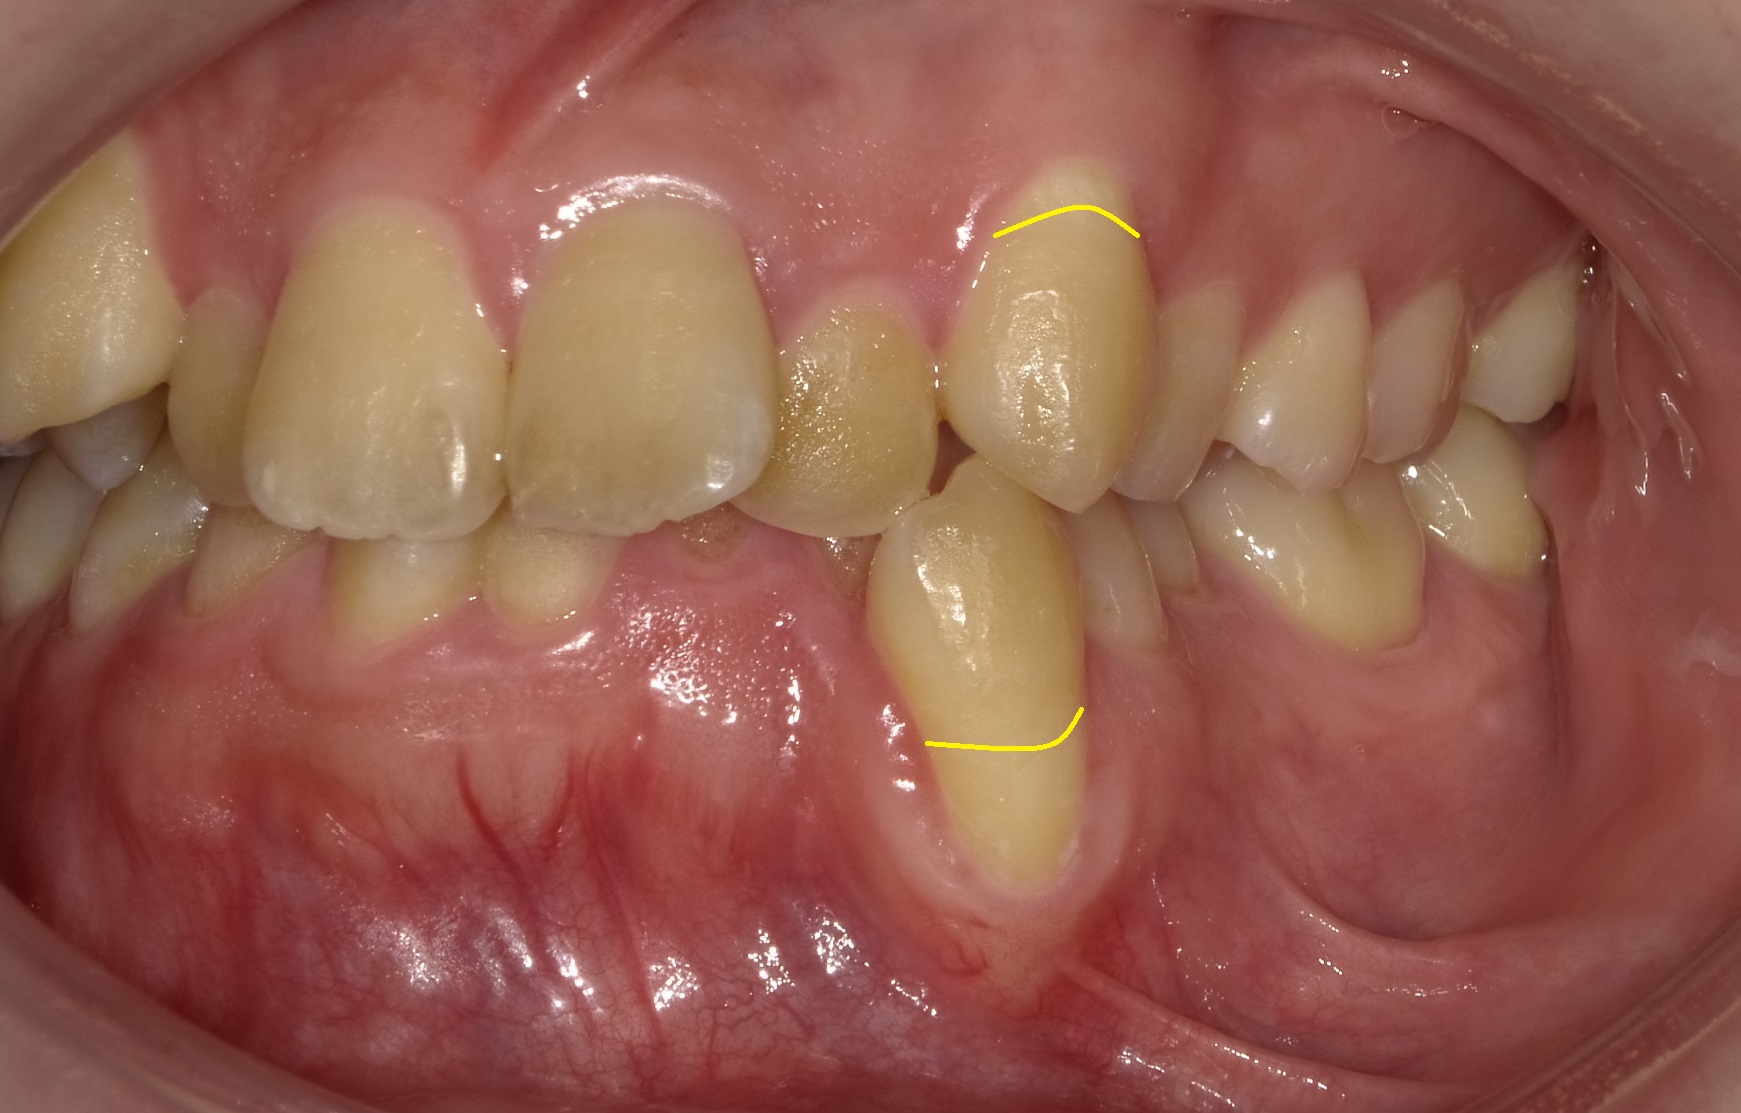

上下の犬歯(八重歯)の本来の歯茎のラインを黄線で引いています。

歯の根っこには表面に歯根膜という細胞の膜が付着していますが、このように露出してしまうと死滅してしまい、結果今後歯並びが良くなっても歯茎のラインが戻ることはほぼ難しくなってしまいます。